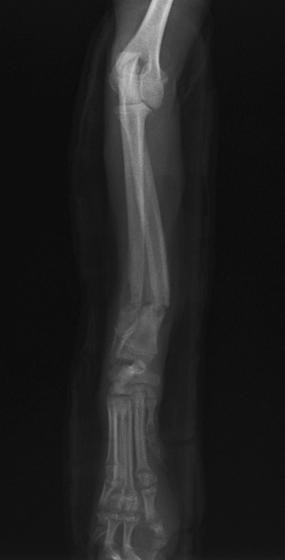

トイプードル 右遠位橈尺骨短斜骨折のALPSによる内固定

症例3:キルシュナーワイヤーのピンニングによる整復

ペルシャ猫 11ヶ月齢 雄

他院にて左大腿骨遠位の成長板骨折(salter-harrisⅠ型)が認められており、治療相談を目的として来院。当院にて、キルシュナーワイヤーを用いたピンニングにより骨折部位の整復を行いました。術後の経過は良好で、現在も経過観察中です。

術前レントゲン

術後レントゲン